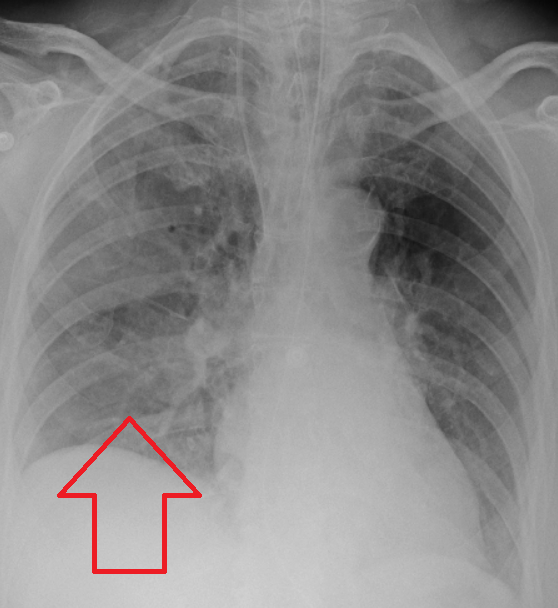

- Chest X-ray

Three common patterns of pneumonia may be detected on chest X-ray which include:

- Lobar pneumonia

- Bronchopneumonia

- Interstitial pneumonia

Aspiration pneumonia classically leads to a right lower lobe abscess (due to the angle of the bronchus), but may present in different lobes.